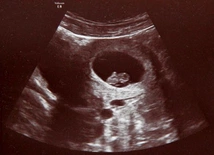

Do niedawna poważne wady płodu oznaczały dramat i brak nadziei. Postęp perinatologii sprawił, że lekarze diagnozują i leczą dzieci w łonie matki - powiedział prof. Przemysław Kosiński. Ale żeby leczyć, trzeba rozpoznać. Dlatego zaleca, by USG wykonywać co najmniej trzy razy w czasie ciąży.